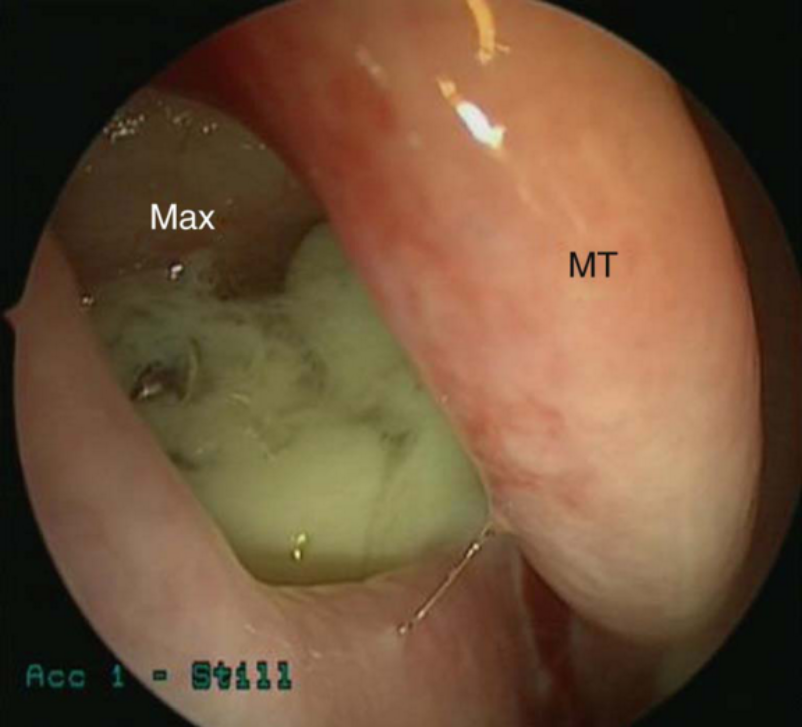

Endoscopic signs include nasal polyps , mucopurulent discharge (primarily from the middle meatus), and mucosal edema (also primarily in the middle meatus). CT findings include mucosal thickening of the paranasal sinuses and osteomeatal complex and fluid or debris in the paranasal sinuses (opacification).

A fungus ball (mycetoma) is a collection of inspissated fungal debris and mucus in an isolated paranasal sinus. Symptoms are similar to CRS or patients can occasionally be asymptomatic. The maxillary sinus is the most common location. Characteristic CT appearance is a heterogeneous hyperdensity within a sinus with microcalcifications. Intraoperatively, fungal balls appearing as a mass of thick, crumbly debris and fungal hyphae are often appreciable. Treatment is endoscopic removal, and antifungal medications are not typically required.